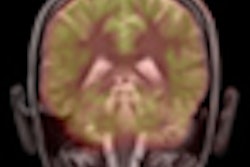

The researchers then investigated the utility of MRI in the study group to compare the results with PiB-PET images. Because MRI can illustrate small-vessel cerebrovascular disease as brightly lit white-matter hyperintensities, the researchers collected T1-weighted, T2-weighted, and proton density MRI sequence information on the study participants.

MRI scans were acquired within six months of the PiB-PET images, and total white-matter hyperintensity (WMH) volume was calculated for each subject. The mean total WMH volume was 5.71 cm3 (median, 2.27 cm3), and total WMH volume did not differ between PiB-positive and PiB-negative individuals.

Among subjects who were positive on the PiB-PET studies, the researchers found increased WMH volume for those with an Alzheimer's diagnosis. Based on a cutoff of 1.25 cm3 total WMH volume, sensitivity was 83% and specificity was 64% in determining which participants had Alzheimer's.